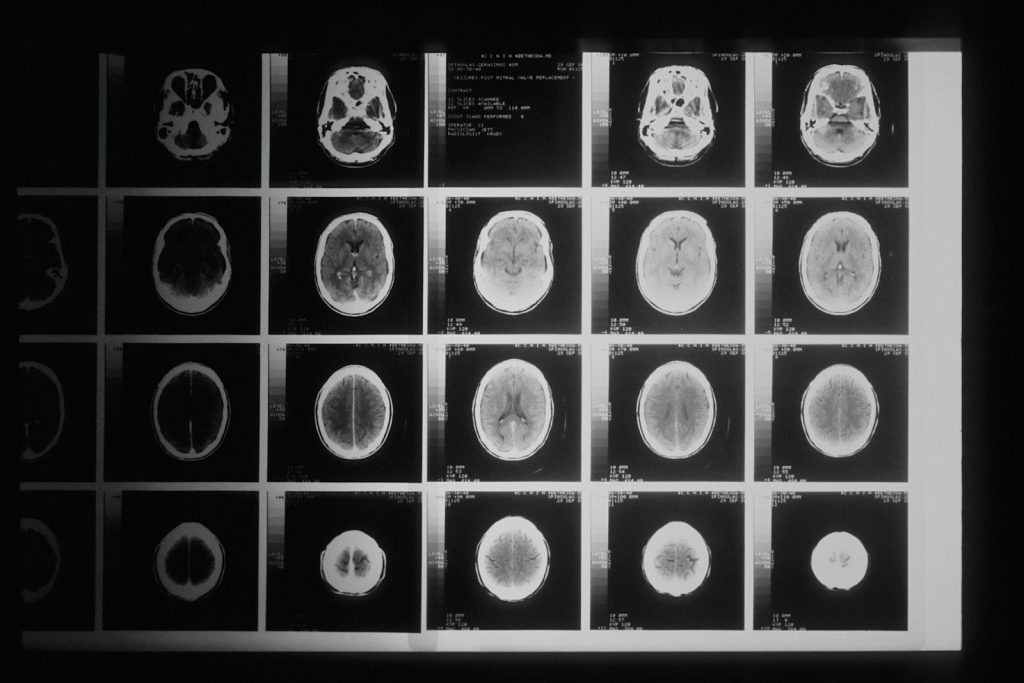

IRM

Pas de rayons X, contraste tissulaire supérieur. Cerveau, rachis, articulations, sein, prostate. Long et coûteux. L’IA commence à diviser les durées d’acquisition par 5 à 10.

Oublie l’image du radiologue tranquille qui sirotе son café en regardant des images. La journée commence souvent dans le dur : les examens urgents de la nuit t’attendent dès l’arrivée : un scanner cérébral d’AVC, un polytraumatisé des urgences, une écho obstétricale qui n’a pas pu attendre. Et derrière chaque image, il y a un médecin qui a peut-être déjà pris une décision en attendant ta lecture. Pas de pression.

Des IRM qui prenaient 45 minutes sont réalisées en 5 minutes grâce à des algorithmes de reconstruction accélérée. Des algorithmes détectent des nodules pulmonaires, des fractures, des sténoses coronaires avec des performances comparables aux experts.